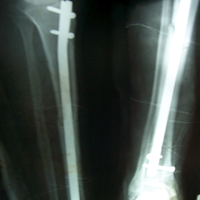

Case:1 Polytrauma Case (Multiple Fractures in Ipsilateral Limb)

Pre-Op Hip (AP & Lateral)

Post-Op Hip

4 Months Post Operative X-ray showing #s united

3 Months Follow up